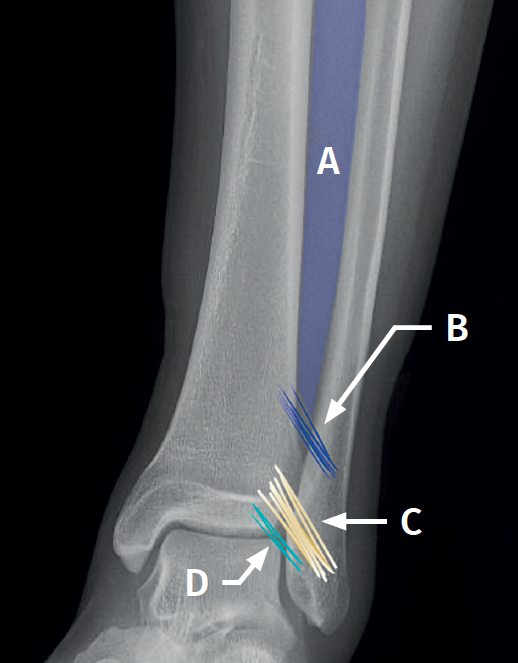

Figura 1. Esquema de la sindesmosis anterior. A: membrana interósea; B: ligamento interóseo; C: ligamento tibioperoneo anterior; D: fascículo distal del ligamento tibioperoneo anterior.